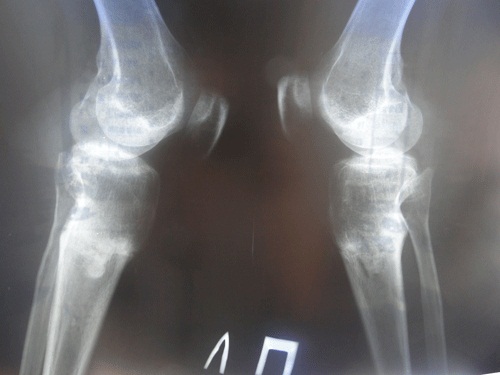

у меня все хорошо,каждый день радуюсь своими ножками) спасибо Вам большое за всё! высылаю Вам фото рентген-снимков через 2 мес после снятия аппаратов. 4 июля было ровно два месяца, на той неделе не успела сделать.снимки сделала сегодня,11 июля.жду Ваших комментарий. по почте снимки нужно высылать или нет?